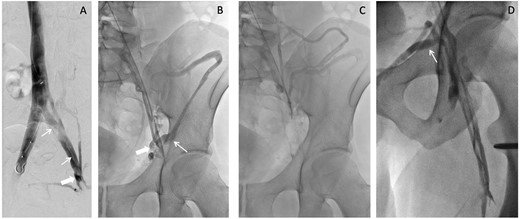

A week after imaging, the patient presented to vascular and interventional radiology for further evaluation of the abdominal varicosities. Varicosities were found along the lower anterior abdominal wall due to formation of collaterals from the inferior epigastric vein. Iliocaval venogram indicated post-thrombotic changes including stenosis (thick white arrow) and synechiae (thin white arrows; Fig. 2). In addition, the patient presented with a small left internal iliac vein with stenosis distally viewed on ultrasound. The radiologist indicated that the left internal iliac appeared to ‘flatten’ under the right internal iliac indicating possible May–Thurner syndrome.

Iliocaval venogram (A) shows post-thrombotic changes including stenosis (thick white arrow) and synechiae (thin white arrows). Left external to common iliac venogram (B) shows collateral drainage pathway via the inferior epigastric vein (thick white arrow) to the contralateral external iliac vein and via the iliac circumflex (thin white arrow). Continued drainage (C) from the iliac circumflex into the iliolumbar and hemiazygos veins is shown. Saphenofemoral venogram (D) shows the sapheno-saphenous collateral drainage occurring via the external pudendal vein (thin white arrow).